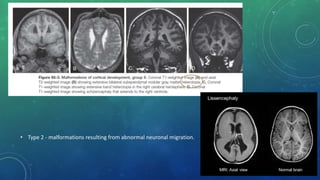

MALFORMATIONS OF CORTICAL DEVELOPMENT

• Type 1 - malformations resulting from abnormal proliferation of neuronal and glial cells.

• Type 2 - malformations resulting from abnormal neuronal migration.